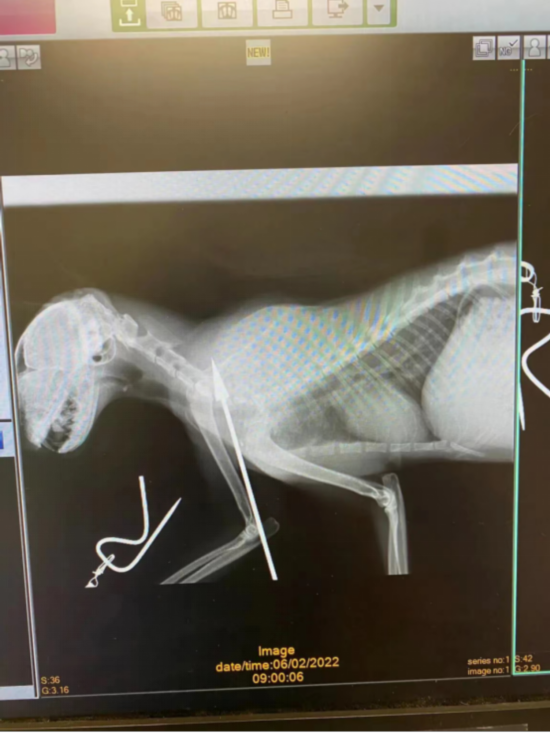

“凯特妮斯”被吹箭射中,图自“KAT慈善组织”脸书

报道称,“KAT慈善组织”发布了其中一只被起名为“凯特妮斯”的雌猫受伤的可怕照片,同时谴责涉事者针对无辜动物的“无意义的、可怕的”暴力。报道称,凯特妮斯接受了治疗,目前正在康复中。

射中“凯特妮斯”的吹箭,图自“KAT慈善组织”脸书